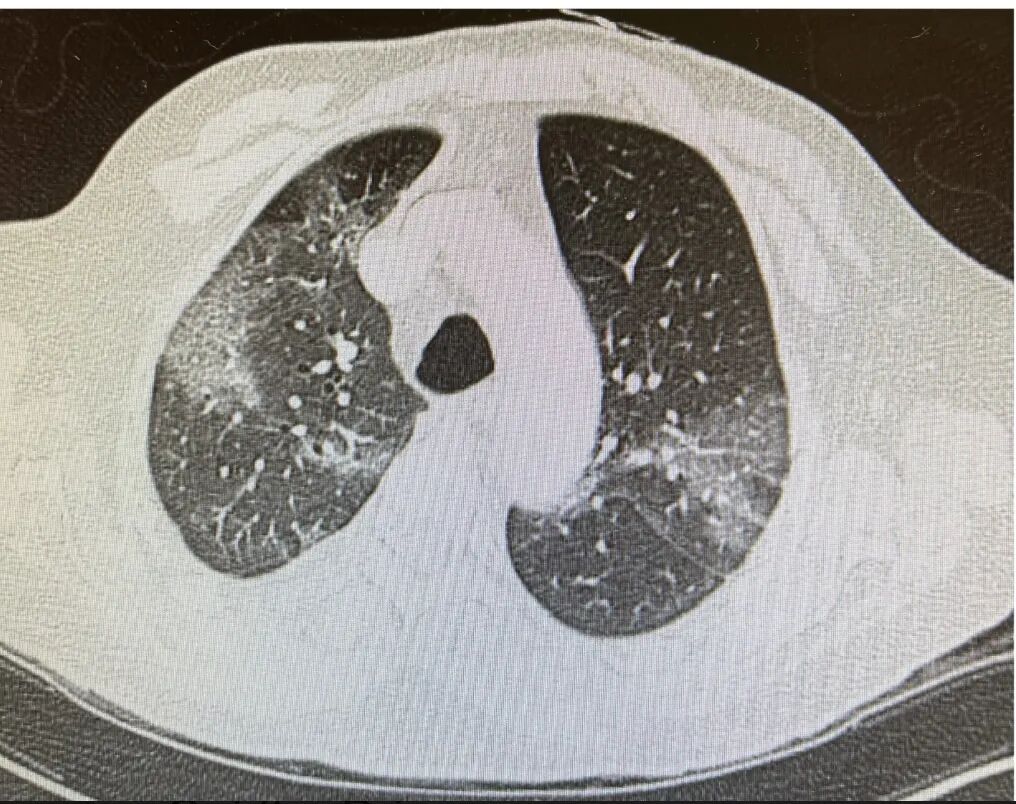

这时立刻做了CT(图1)。大家都应该很熟悉这样的图像,我再强调一下,新冠的CT图像特征是毛玻璃影,但毛玻璃影本身不是特征,关键它是片状的、外周分布型的毛玻璃。我选的这个截面偏高,因为要和后面的一张CT来做比较,实际患者的毛玻璃影从肺尖一直到肺底全都有,在肺底部更重一些。

图1:COVID-19 CT影像